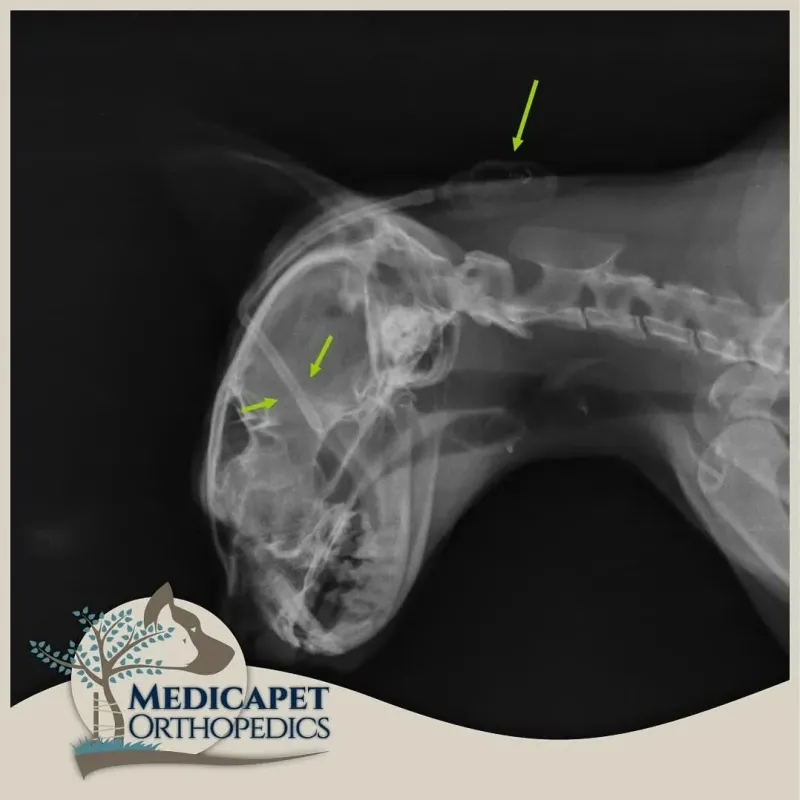

Bazı olgularda net bir semptom göstermeyen hidrosefalinin ayırıcı tanısı güçtür. Çünkü beyinle ilgili pek çok problem aynı semptonlara sebep olabilir. Fakat laterale, yani dışa doğru kaymış göz küreleri hidrosefali için tipiktir. Yavru kedi ve köpeklerdeki kubbe şeklindeki kafatası da hidrosefaliden şüphelenmek için yeterlidir. Bu durum bazı platformlarda ‘’Down Sendromlu Kedi’’ gibi ifadelerle gösterilse de kedilerde Down Sendromu bulunması açıkça imkansızdır. Çünkü Down Sendromu insanların sahip olduğu 23 çift kromozomun 21.sindeki bir bozukluktan meydana gelirken kedilerde 19 çift kromozom bulunur. Bu durumda Down Sendrom’lu gibi görünen kediler çok yüksek ihtimalle hidrosefali hastasıdır.

Teşhis

Teşhis seçeneklerinden önce şunun çok iyi bilinmesi gerekir ki: HYDROCEPHALUS’UN ERKEN TEŞHİSİ HAYATİ ÖNEM TAŞIR! PEK ÇOK VAKADA SAATLER BİLE ÖNEMLİDİR. VAKİT GEÇİRİLMEDEN MÜDAHALE EDİLMELİDİR.